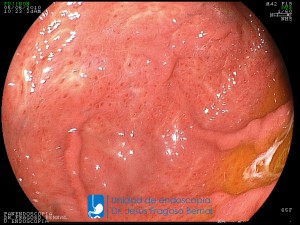

La Unidad de Endoscopía fue creada en 2002 por el Dr. Jesús Fragoso Bernal, es pionera en el estado por la utilización de la tecnología más avanzada, que nos permite ofrecer servicios integrales de diagnóstico y tratamiento para las enfermedades del aparato digestivo.

El profesionalismo de nuestro personal, altamente especializado, se distingue por la calidad y calidez de nuestros servicios con el objetivo de brindar una atención de excelencia en el ambiente más confortable para comodidad y seguridad de nuestros pacientes.

"La Unidad de Endoscopía se ha caracterizado por un progreso continuo desde su inicio marcando la pauta en los procedimientos endoscópicos en el estado de Tlaxcala y estando siempre a la vanguardia tecnológica."

Dr. Jesús Fragoso Bernal